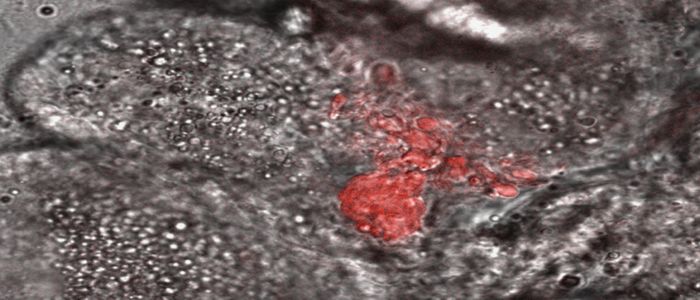

Research on brain swelling in children with cerebral malaria reveals potential new treatment approach